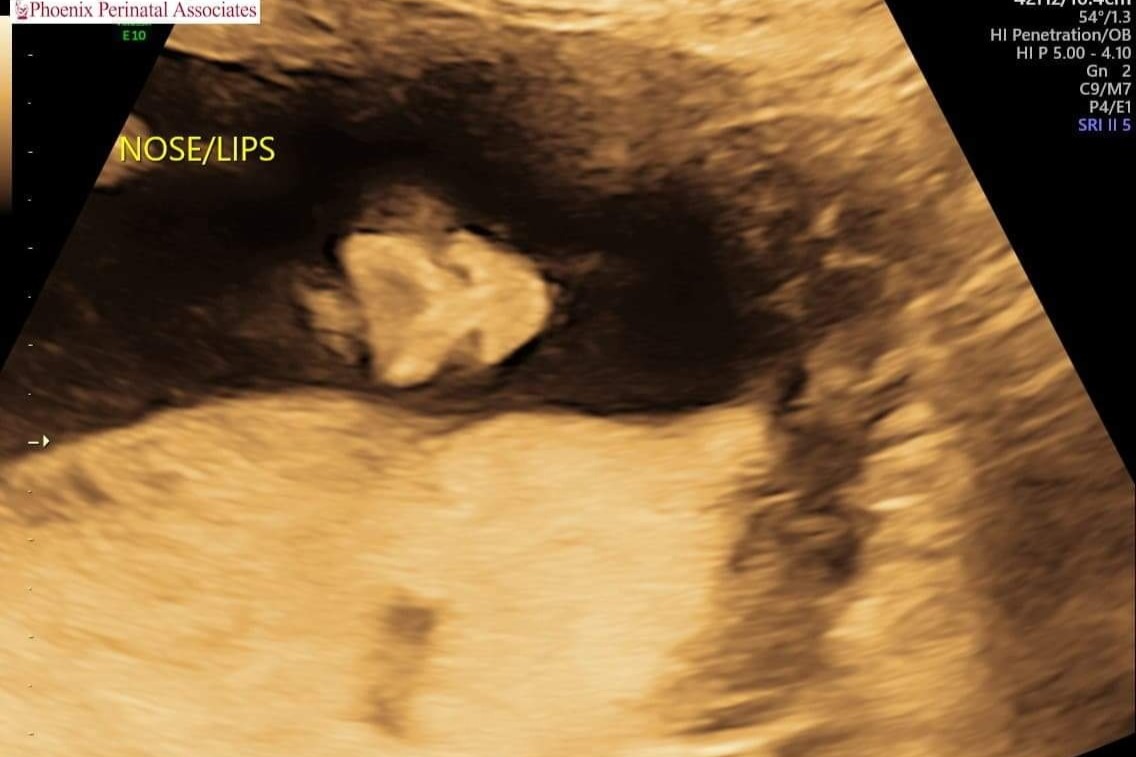

On Tuesday May 11th 2021 our family received fateful news that any expecting parent dreads hearing: our baby has a birth defect. Spina bifida myelomeningocele, a rare neural tube defect that causes baby's spine to not fuse properly which results in their spinal cord, nerves, and spinal fluid to pool outside of the spinal column. Common issues with this include paralysis, ambulatory, and developmental difficulties.